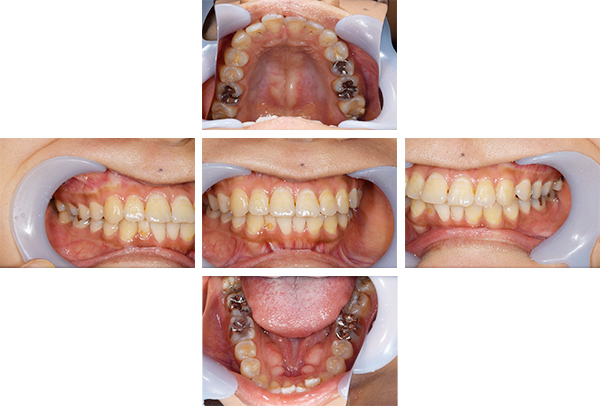

インレー症例

初診時パノラマ

初診時口腔内写真

iTero NIRI機能による診査

虫歯除去後

初診時バイトウィングデンタル

レントゲンだとちょっと虫歯が怪しいくらいに写っている。これだけだと確定診断としては、判断材料が少ないと考えられる。

黄色丸の部位が、他の部位と違って白く抜けがあるのがわかります。これがNIRI機能による虫歯の診査です。

この機能のおかげで、歯と歯の間の見つけにくい虫歯がよくわかるようになってきました。

In(インレー)セット後

当院では自費のインレー(つめ物)の場合、ゴムのシートをかけてから詰めていきます。

ゴムのシートをすることで、歯面を最大限乾燥することができ、接着力が上がる他、操作時の材料の誤飲の防止、接着剤の歯肉縁下(歯ぐきの中)への侵入を防止するなどといったメリットがあります。(歯の並びによっては、ゴムのシートができないことがあります。また、シートをかけることで苦しくなる、苦手という方には無理に行いません。)

年齢・性別 40代・男性

主訴 左上の奥歯がしみることがある

治療内容 左上4の虫歯

治療期間 2週間

リスク・副作用 虫歯の大きさによっては、神経をとらないといけなくなることがあります。

また、虫歯が大きかったケースで神経を残した場合、治療後にしみるなどの

症状が続くことがあります。

費用 ・ジルコニアインレーで修復

55,000円

治療方針

IOSのNIRI機能によって虫歯部分が明らかになったので、虫歯を除去後に修復治療を行うこととしました。

特記事項

ラバーダムは歯とつめ物をくっつける際に非常に効果的です。

人間は呼吸をしますので、お口の中はかなり湿度が高くなっています。水が多い状態でものをくっつけようと思ってもなかなかくっつかないということと同じになります。

ですので、呼気中の湿度に左右されないようにするために、ラバーダムを用いて接着力を高くしています。

ラバーダムで息が苦しくなる場合は使用しませんし、ラバーのアレルギーがある場合も使用できません。

担当医師所見

虫歯の有無を確認する上で今まではレントゲンと自分の目での確認でした。現在は目で見るよりもはるかにわかりやすいIOSという装置がありますので、虫歯の発見がしやすくなりました。

そのため、患者さんの虫歯の進行の段階が早いうちにわかる様になり、神経をとらなければならないというケースが非常に少なくなっています。